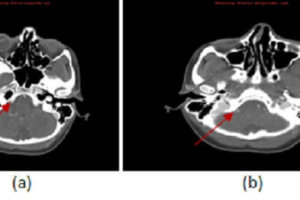

Vertebral Artery Dissection, CTA

Carotid/vertebral artery dissection is an underdiagnosed disease that can result in substantial morbidity. It has an incidence of 1-1.5/100000 and disproportionately affects young patients. Diagnosis is challenging clinically because the symptoms are... Read more »